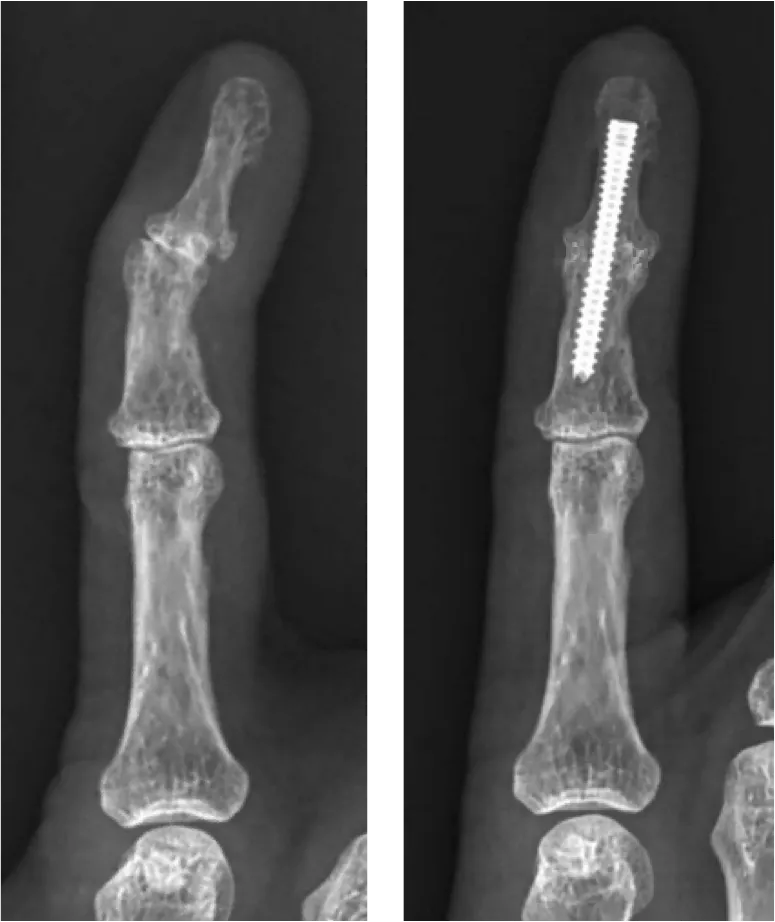

- Röntgenonderzoek: op een röntgenfoto van de hand of vinger zijn de kenmerkende veranderingen bij vingerartrose zichtbaar. Men ziet versmalling van de gewrichtsspleet, botuitsteeksels (osteofyten) en soms kleine cystes in het bot onder het gewricht. Deze foto bevestigt de slijtage in het vingergewricht en helpt de ernst te beoordelen.

Als een vingergewricht door de vingerartrose zeer pijnlijk en stijf is ondanks eerdere behandelingen, zijn er enkele chirurgische opties:- Arthrodese (vastzetten van de vinger): het aangedane gewricht wordt in een licht gebogen, functionele stand vastgezet. Door het vastzetten van de vinger verdwijnt de pijn vrijwel volledig, maar het gewricht kan niet meer bewegen.

Bij een arthrodese wordt het versleten gewricht in een functionele stand vastgezet met een schroef. De pijn verdwijnt vrijwel volledig, maar het gewricht beweegt niet meer. Een vingerprothese vervangt het gewricht door een implantaat (meestal silicone) waardoor de beweeglijkheid behouden blijft. Voor het eindkootje (DIP) verkiest men meestal een arthrodese; voor het middelste kootje (PIP) wordt vaker een vingerprothese geplaatst.